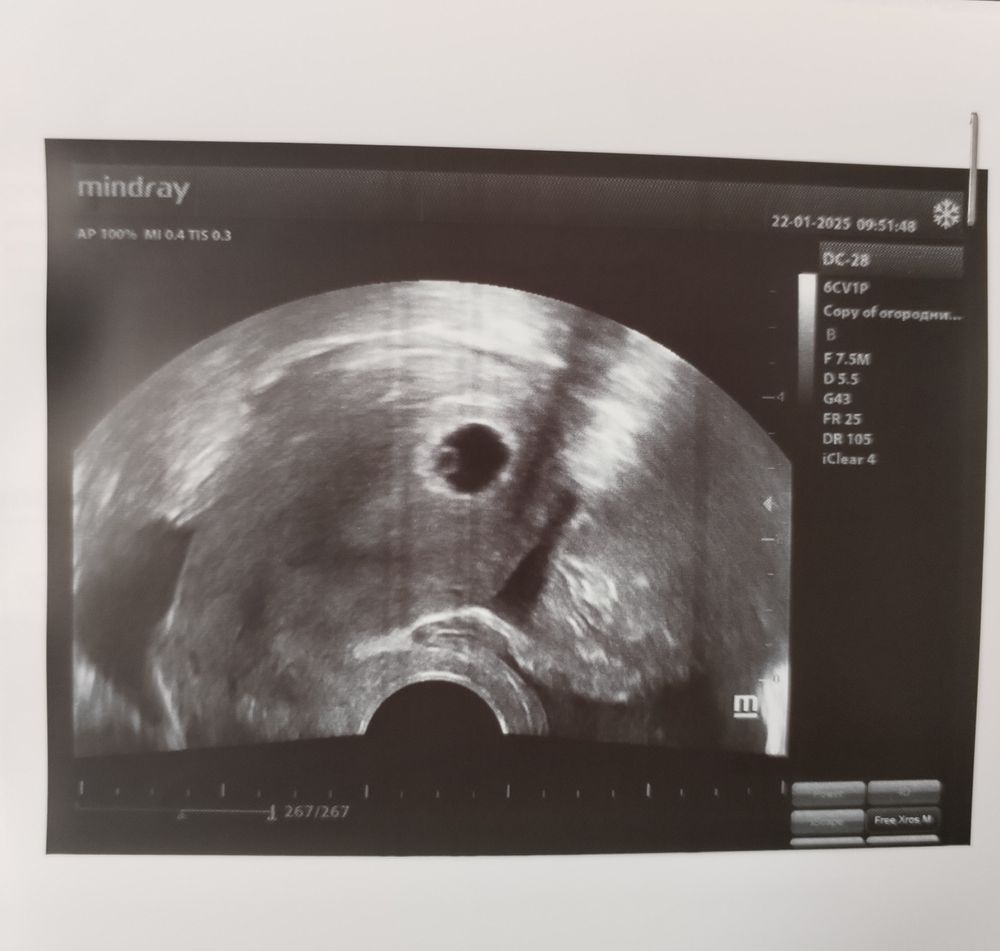

Первое УЗИ 5+4

Нашли плодное яйцо в матке,ура! Очень боялась внематочной, живот тянуло то там, то тут. Желточный мешок есть, но эмбрион пока не видно. Док сказал через неделю - полторы можно будет прийти послушать СБ. Я так счастлива, теперь поставлю беременный кружок 🙌